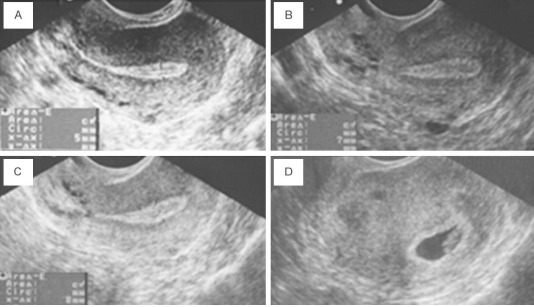

B. Endometrial Rejuvenation with IVF or ICSI (A Thin Endometrium)

- In some women undergoing IVF or ICSI, the endometrial thickness remains below the optimal level (< 7mm) despite hormone replacement therapy (HRT). Thin endometrium can lead to the cancellation of the embryo transfer cycle, reducing the chances of pregnancy.

- PRP therapy (0.5-1ml) is used in such cases, where it is infused into the uterine cavity on the 10th day of the HRT cycle. If there is no improvement in endometrial thickness after 72 hours, additional PRP infusions are performed.

- Once the endometrial thickness exceeds 7mm, embryo transfer is conducted. Studies have shown improved endometrial growth and pregnancy rates in women after PRP therapy.

Fig 5